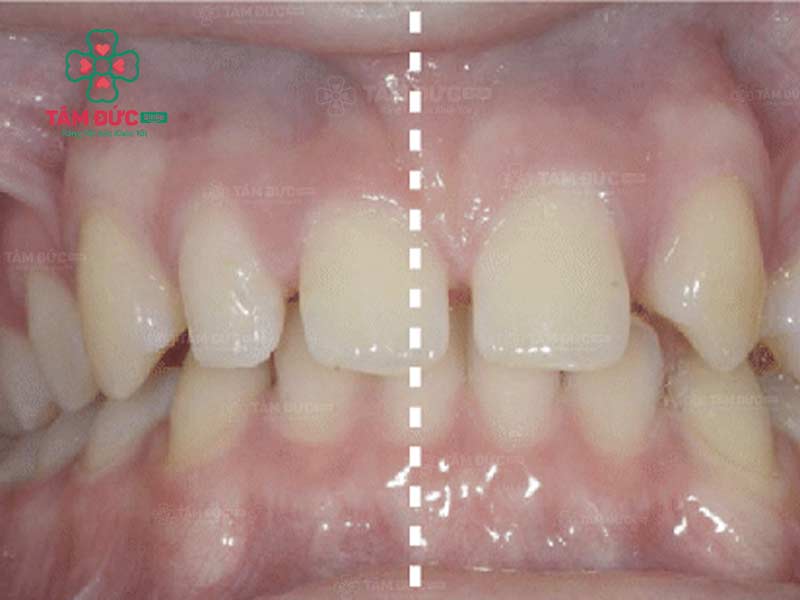

Răng lệch nhân trung là tình trạng kẽ giữa hai răng cửa không nằm thẳng với đường nhân trung. Đường nhân trung là một đường rãnh nhỏ nằm ở giữa mũi và môi trên. Ở người bình thường, kẽ giữa hai răng cửa sẽ nằm ngay trên đường nhân trung. Tuy nhiên, trong một số trường hợp, kẽ giữa hai răng cửa có thể lệch sang trái hoặc phải so với đường nhân trung.

Cách nhận biết Quý khách đang bị lệch nhân trung:

- Nhìn trực tiếp: Quý khách hãy nhìn trực tiếp khuôn mặt của mình trong gương. Nếu Quý khách thấy kẽ giữa hai răng cửa lệch sang trái hoặc phải so với đường nhân trung thì đó là dấu hiệu bị lệch đường giữa.

- Sử dụng thước đo: Quý khách hãy dùng thước đo để đo khoảng cách giữa kẽ hai răng cửa và đường nhân trung. Nếu khoảng cách này không bằng nhau thì đó là dấu hiệu của lệch nhân trung.

Trường hợp bị lệch nhân trung